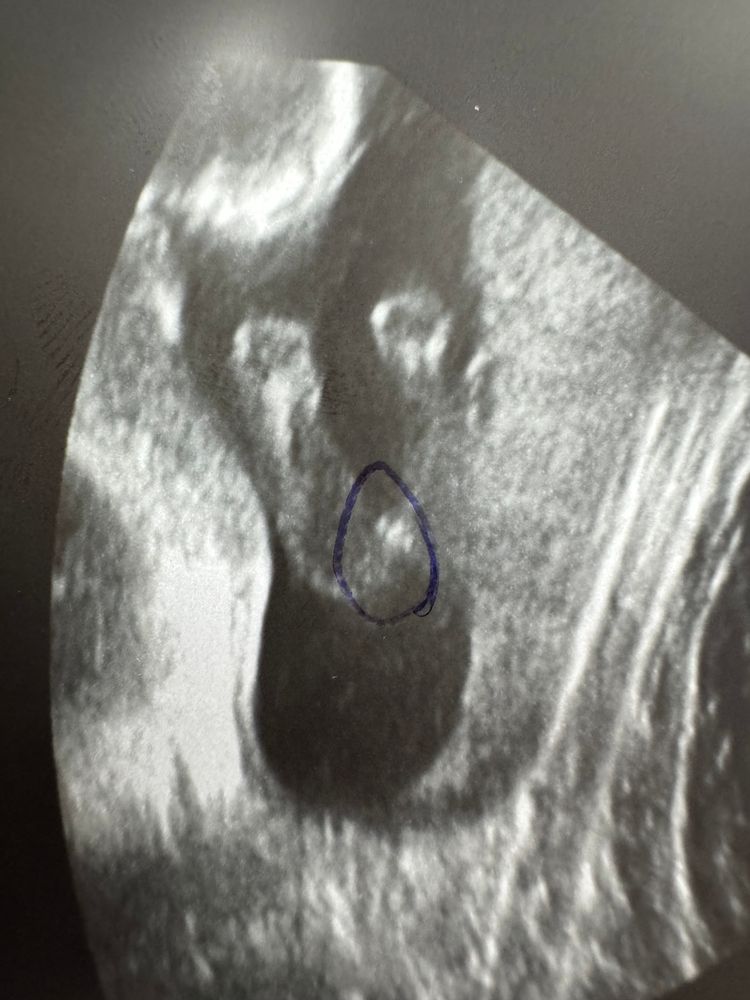

Пол на 18 неделе беременности

Кнопик , девочка

Кнопик , девочка 😌

У нас будет девочка!🩷 Пол ребёнка на узи 🧬